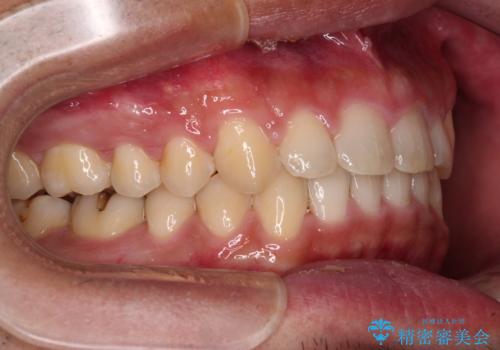

深い咬み合わせと隙間の空いた歯列をワイヤー矯正で改善

- 前歯の隙間と深い咬み合わせを改善したいとのことで来院された患者様です。

奥歯の咬み合わせは理想的な状態であったため、ワイヤー矯正でもインビザラインでも比較的容易に対応可能でした。